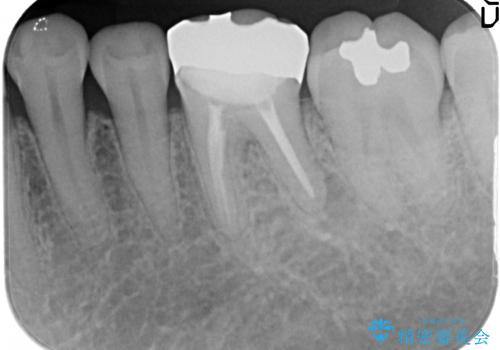

- 他院にて左下6の再根管治療を勧められ当院にいらっしゃった方の症例です。

再根管治療終了後、オールセラミッククラウンにて補綴を行いました。